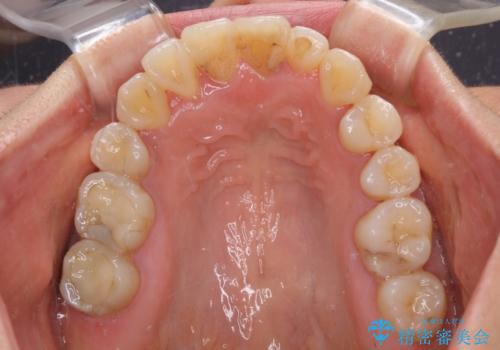

狭い上顎骨を拡大 著しい叢生を抜歯矯正で改善

- 上顎の著しい叢生と奥歯の咬みにくさを気にして来院された患者様です。

治療途中、長期間海外旅行をされたり、帰国後には遠方へ転居されたりと、治療期間が伸びましたが、2年強で治療を終えることができました。